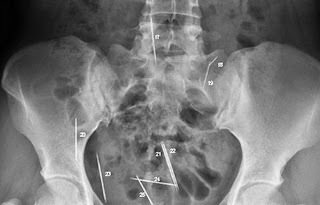

OBJETOS INTRACORPOREOS

La primera radiografía es la de un hombre que presenta un bisturí en su cavidad abdominal, este elemento quirúrgico como lo dice su nombre fue olvidado por los médicos cirujanos a la hora de terminar una operación. Me impresiona un poco la forma en la que el ser humano es capaz de sobrevivir con objetos que no pertenecen a nuestro organismos, tal vez estoy atribuyendo una cualidad de supervivencia a las personas, pero también doy como hecho una posible casualidad a que esta persona siguiese vivo, suerte, tal vez no era su hora todavía de morir, el señor tenía muchas defensas y un sistema inmunológico activo que no dejo avanzar tanto una infección al punto de quitarle la vida. Son muchas la hipótesis de la adaptación a un bisturí y también muchas las preguntas de ¿cómo este llego a ser olvidado por un personal médico?

Siguiendo con las radiografías encontré casos impresionantes de objetos como ajugas, tijeras, dispositivos electrónicos, dentro de diferentes partes del cuerpo. La forma en la terminaron estos objetos tienen diferentes motivos algunos por accidente, otros por negocio y por hacerle daño a estas .Algunos ni se enteraban que tenían estos objetos y vivieron gran parte de su vida con ellos.